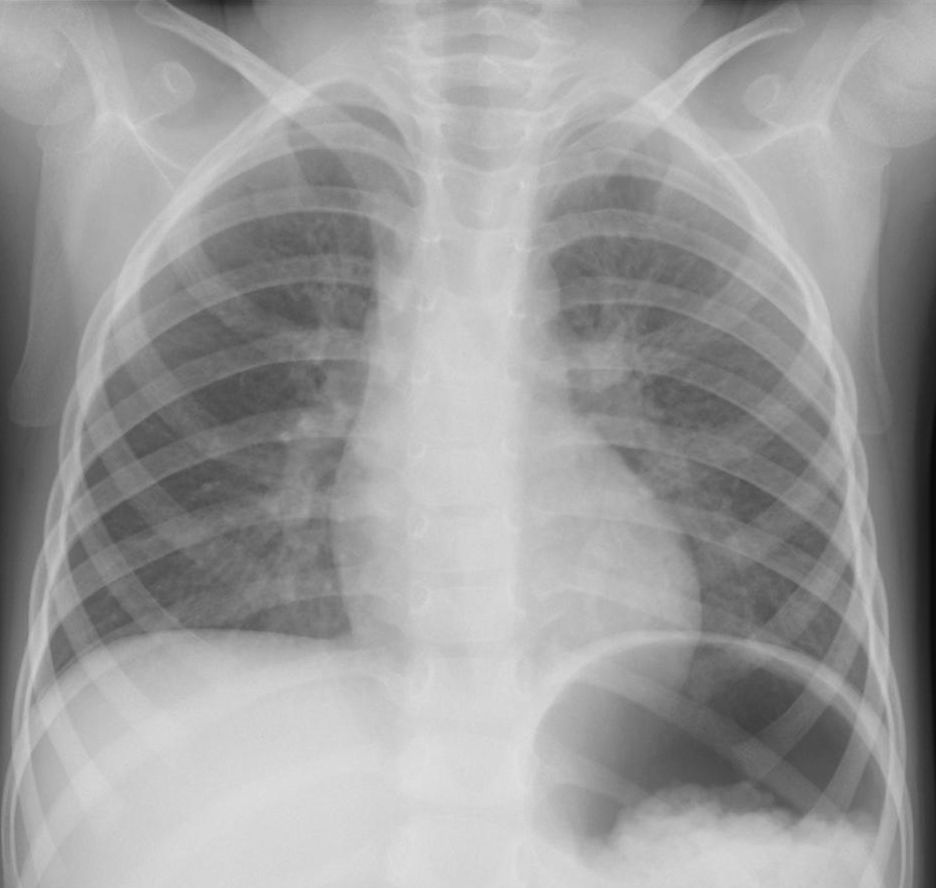

A.正常像(成人) 読影のチェックポイント さらに詳細に読影 最低限の読影項目 以上を参考に実際に上の正常像を読影

①左右対称、適切な黒化度・コントラストで撮影されている。

②胸郭、横隔膜に異常みとめず正しく吸気位である。

③鎖骨、気管、縦隔、心陰影、脊椎(胸椎・頸椎)、大動脈弓、続く胸部大動脈は異常をみとめず。

④肺野は左右とも透過度は良好、肺門ならびに肺動脈、気管支の走行は正常。

⑤右上葉と中葉の葉間の葉間間裂の線状影がみられるが、肺の異常影は(孤立性陰影を含む)みとめられない。

⑥心陰影は右辺縁・左辺縁ともに正常、心拡大もみられない。

[評価] 撮影条件は良好、異常陰影等みられず正常のレントゲン像。